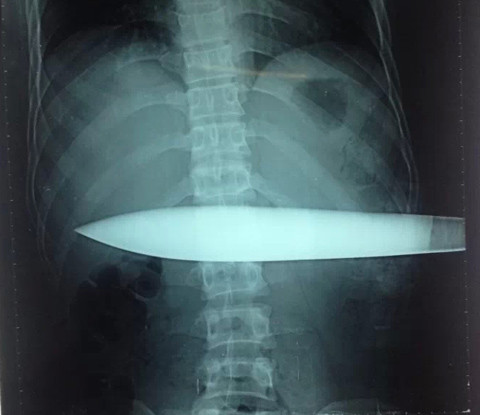

Nạn nhân B.V.T. nhập viện cấp cứu với con dao còn cắm trên người - Ảnh: Bác sĩ cung cấp

Nạn nhân được chuyển đến Bệnh viện Việt Đức trong tình trạng con dao có lưỡi dài khoảng 30 cm cắm từ mạng sườn trái ngập sâu vào phần ngang bụng. Ngay sau khi làm các thủ tục cần thiết bệnh nhân đã được chuyển mổ cấp cứu.

Các bác sĩ cho biết, tại thời điểm vào viện, bệnh nhân còn tỉnh với con dao nhọn dài khoảng 50 cm, trong đó phần lưỡi khoảng 30 cm, cắm ngập sâu trong cơ thể.

Hình ảnh X-quang cho thấy con dao đâm gần hết phần bụng của nạn nhân - Ảnh: Bác sĩ cung cấp

Hình ảnh phim chụp X-quang chưa thể đánh giá hết được tổn thương vùng bụng, tuy nhiên tình trạng sức khỏe của bệnh nhân khá nguy kịch. Bệnh nhân T. ngay sau đó đã được chuyển vào phòng mổ cấp cứu để rút dao ra khỏi cơ thể.